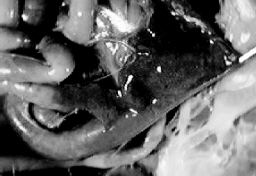

| Figure 39. Turkeys dying with haemorrhagic enteritis commonly have the small intestine distended with blood. In this case a loop of intestine has been opened to show the blood. |